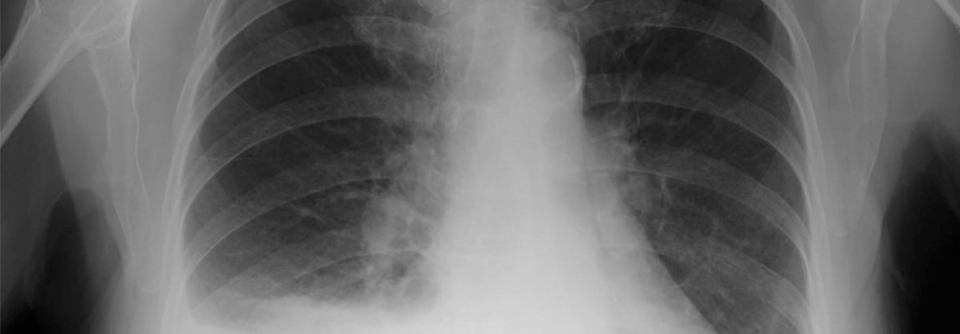

Inwieweit bei Verdacht auf einen malignen Pleuraerguss ein beschleunigtes Vorgehen mit früher Biopsie sinnvoll und machbar ist, wird derzeit in der ­STREAMLINE-Studie geprüft. Inwieweit bei Verdacht auf einen malignen Pleuraerguss ein beschleunigtes Vorgehen mit früher Biopsie sinnvoll und machbar ist, wird derzeit in der ­STREAMLINE-Studie geprüft. © Kyrylenko – stock.adobe.com

Bislang steht die Pleuraaspiration im Mittelpunkt, wenn es um die Abklärung eines Ergusses geht. Vor allem bei Verdacht auf Malignität sollte man mit einer bildgestützten Biopsie jedoch nicht zu lange warten, um Betroffenen fortbestehende quälende Atemnot zu ersparen.